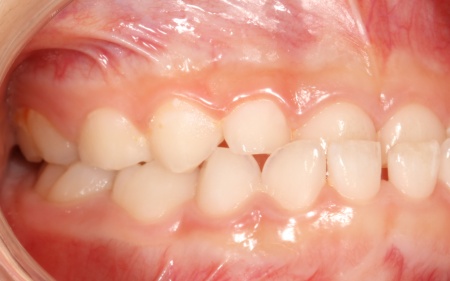

治療後

お子様の成長に合わせて慎重に治療を進めることで、無理のない自然な形で歯並びと噛み合わせを改善することができました。

矯正治療が終了したあとは、治療後の状態を安定させて後戻りを防ぐための「保定装置」を装着し、経過観察を行います。

この段階でも定期的に通院いただいて、良好な状態が維持されていることを確認しました。

現在も保定装置を継続して使用していただいているため、安定した状態を保っています。